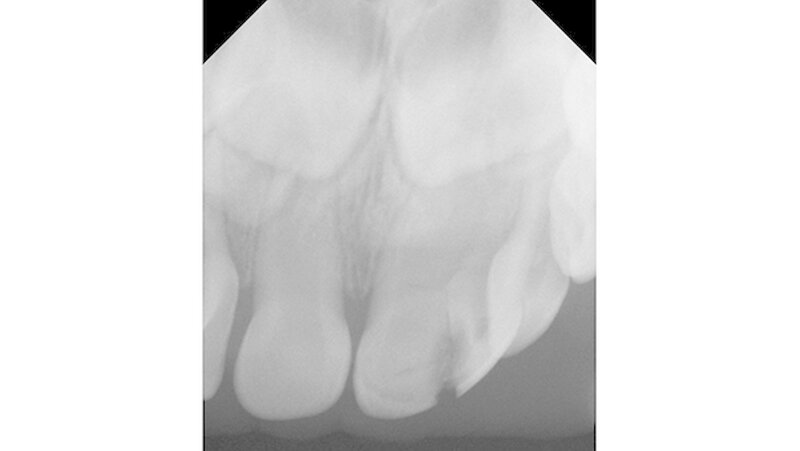

Nach Durchführung der zahnbezogenen Diagnostik inklusive Röntgen wurde die Diagnose komplizierte Kronenfraktur eines Zwillingszahns 61a/61b gestellt. Zur Abschätzung der Kooperation und Desensibilisierung für eine potenzielle Behandlung wurden die Zähne des Kleinkindes mit einem rotierenden Bürstchen geputzt.

Die Extraktion gestaltete sich aufgrund der besonderen Anatomie erwartungsgemäß deutlich schwieriger als bei einem gewöhnlichen Milchfrontzahn, konnte aber zügig und komplikationslos erfolgen. Bei den Folgebesuchen wies das Kind weiterhin eine altersgerechte gute Mitarbeit auf.Dr. Julian SchmoeckelZZMK Universität GreifswaldAbt. für Präventive Zahnmedizin & KinderzahnheilkundeDep. Preventive & Pediatric Dentistry, University of GreifswaldWalther-Rathenau-Straße 42, 17475 Greifswald, Germanyjulian.schmoeckel@uni-greifswald.de